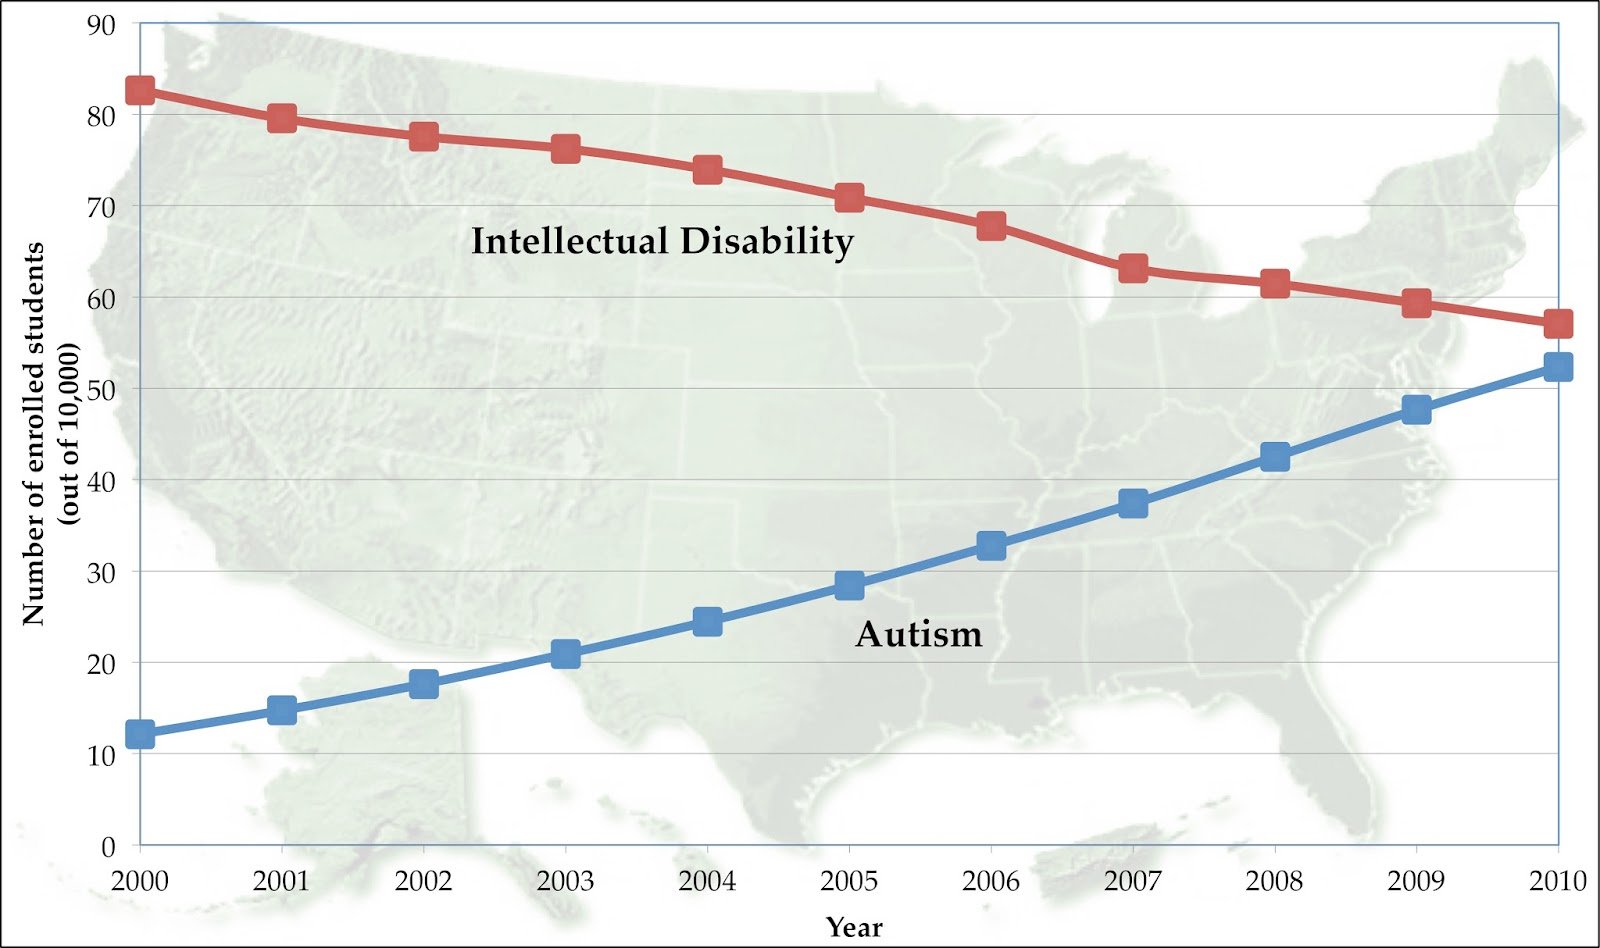

Kennedy Jr. Blames Toxins for Autism Rise

## Kennedy Jr. Claims Environmental Toxins Drive Autism Increase; Experts Disagree Washington, D.C....

CDC: Autism Diagnoses Rise Among US Children

## CDC Report Shows Rise in Autism Diagnoses Among US Children, Sparking Debate **Atlanta, GA** –...

Autism Diagnoses Rise Among US Children

## Autism Diagnoses Rise Among US Children: Improved Detection or Cause for Concern? **Atlanta, GA*...